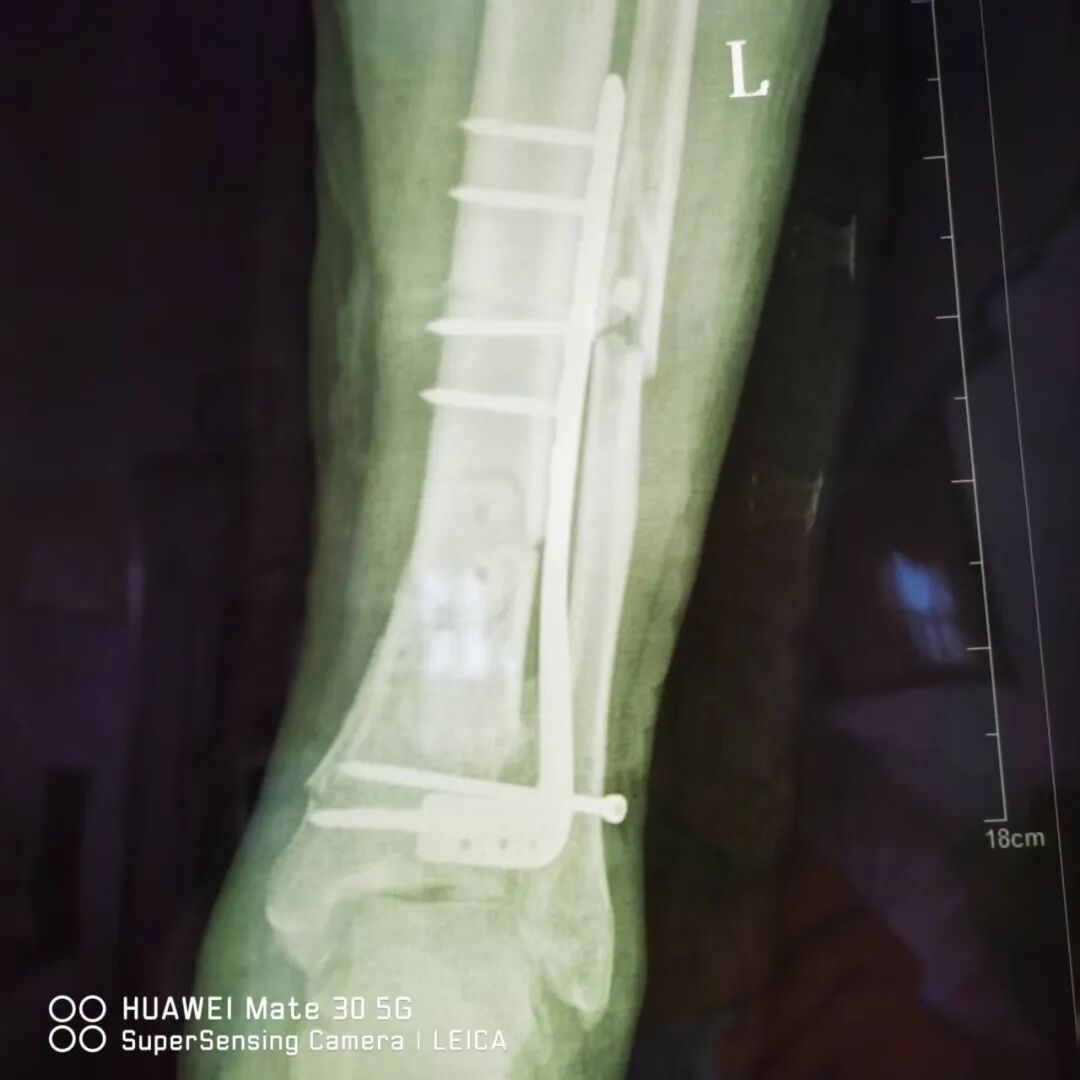

近日,阳光医院骨科成功为一名严重踝部摔伤患者分期实施手术。通过分阶段治疗策略有效解决复杂伤情,为患者康复奠定坚实基础。 患者赵XX在给房子换石棉瓦不慎摔下来,当时左小腿疼痛并流血,不能活动,伤口内骨折端外露,家人紧急将他送至阳光医院救治。 01 左踝关节骨折(Pilon骨折,AO分型C3) 经急诊摄片检查示:患者左胫骨远端粉碎性骨折,左腓骨中下段骨折(Pilon骨折,AO分型C3),同时伴有大面积皮肤软组织坏死及血管神经损伤,若直接进行骨折复位固定,感染风险极高且不利于伤口愈合。因骨折情况复杂,手术难度较大,我院骨科团队迅速组织多学科会诊,结合患者伤情特点,制定“清创维稳-骨折复位固定”的分期手术方案。 02 分期手术 第一阶段(急诊期),骨科团队优先对创面进行彻底清创,清除坏死组织并妥善处理血管神经损伤,鉴于开放性骨折创面污染重、感染风险高,同期行左胫腓骨骨折复位外固定架固定手术。术后予积极抗感染、对症治疗及精心护理,在医疗团队及家人支持配合下,伤口愈合良好。 第二阶段(二期手术内固定,一期术后2周),待软组织条件稳定后,骨科团队为患者行切开复位L型锁定钛板内固定术,术中同期取同侧髂骨行自体骨移植,术前术后均行影像学检查学评估。两次手术方案合理,衔接紧密,团队配合良好,术中实现骨折部位精准复位与可靠固定,治疗顺利完成。 术 后 目前,患者伤口愈合良好,骨折部位稳定性显著提升,已进入系统康复训练阶段。骨科主任董庆武表示:“分期手术策略可最大程度降低严重创伤的并发症风险,保障手术安全性与治疗效果。此次成功治疗展现了我院在复杂创伤救治领域的综合实力,也为同类病例提供了宝贵经验。”